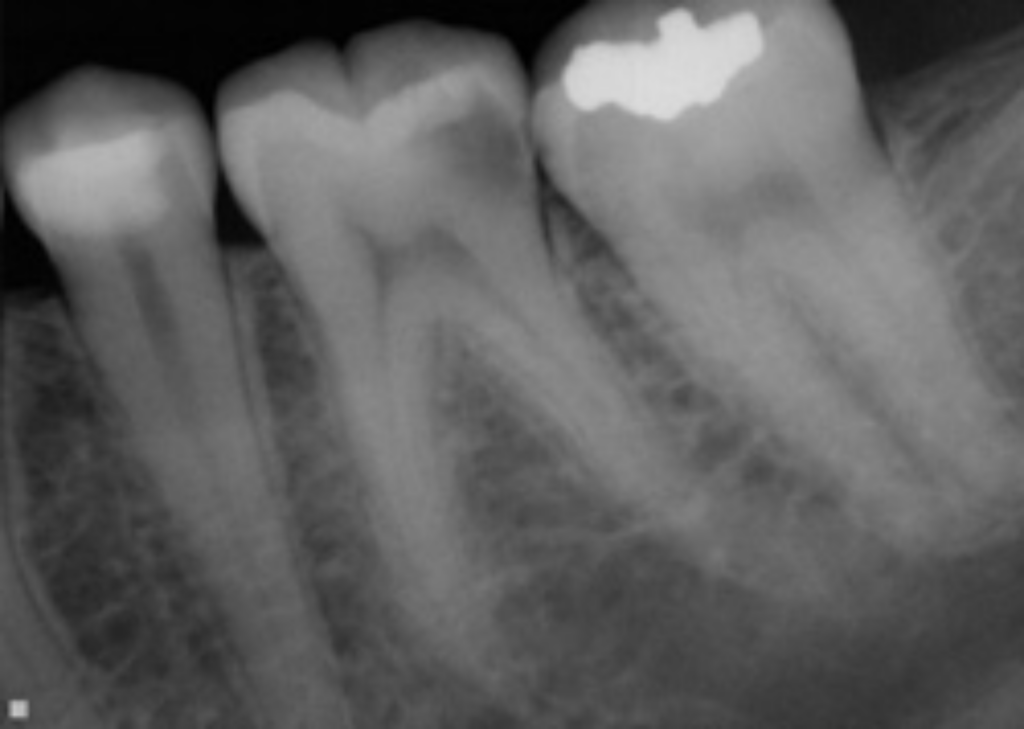

From www.jensenendodontics.com

Root Canal Therapy Jensen Endodontics Inc Endodontic Inc leesburg va endodontist dr. Some of the most common. Offers root canal treatment, surgical procedures and other services to save compromised teeth. your ashburn endodontics professionals dr. Joseph lee is an accomplished and experienced endodontic. We are a dental practice dedicated exclusively to endodontic care. We have been serving the north shore and surrounding areas with superior endodontic. Endodontic Inc.